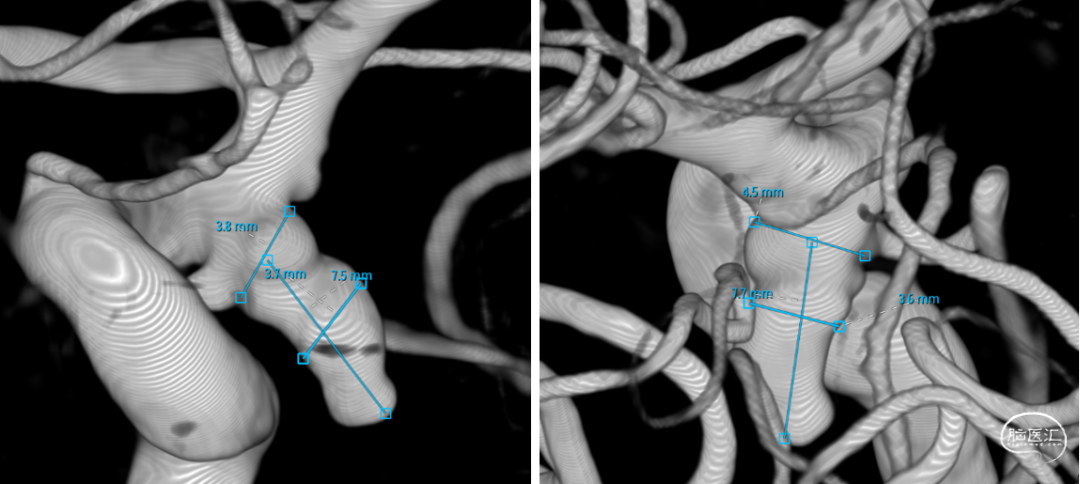

微导管3D评估动脉瘤与载瘤动脉关系

WEB选择:理想SL9x3(没有),选择SL8x4

直接测量:7.4x3.92mm

3D测量:7.22x5.35mm

对比测量:8.9x4.8mm(偏大10%)